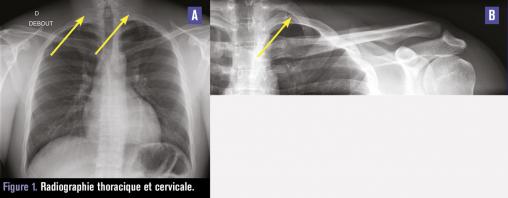

Ce jeune engagé de 21 ans consultait pour une douleur persistante du membre supérieur gauche avec hypotonie, hypoesthésie et paresthésie pour tous mouvements bras levé gauche et lors du port d’un sac à dos. L’examen clinique au repos était sans particularité. Le test d’Allen (position « haut les mains », menton levé, rotation controlatérale de la tête, inspiration profonde) et le test de Roos (position « haut les mains », mouvements lents de fermeture et ouverture de la main) étaient positifs dès 40 secondes avec reproduction de symptômes. Les tests musculaires étaient normaux. L’imagerie (radiographie cervicale [fig. 1], arthrotomodensitométrie [fig. 2], angio-imagerie par résonance magnétique [IRM] et électromyogramme [EMG]) montrait des côtes cervicales surnuméraires. Le bilan neurovasculaire était normal. Une simple éviction des situations à risque avec rééducation a résolu la doléance.

Une côte cervicale surnuméraire est présente chez 0,5 % de la population ; 10 % des patients sont symptomatiques et 9 % justifient une décompression chirurgicale.1 Lié à la compression du plexus brachial, le tableau clinique prend la forme d’un syndrome du conflit thoracique très variable (douleur, paresthésie, faiblesse du membre) lors de l’élévation prolongée du bras. Les tests cliniques sont peu spécifiques et sensibles et justifient de les associer (Adson, Allen, Roos). L’imagerie réalisée comprend radiographie cervicale, IRM et EMG notamment. Une kinésithérapie (protocole de Peet), des injections de corticoïdes, voire une chirurgie de décompression (scalénectomie, exérèse costale) peuvent être nécessaires.2